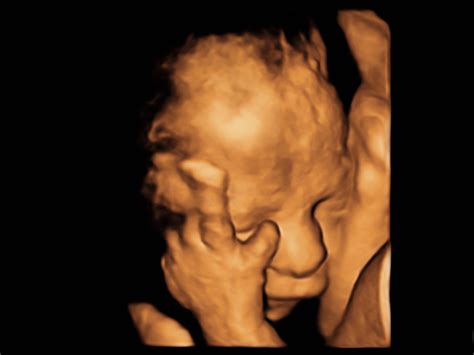

Fetálny vývin (od 9. týždňa do pôrodu)

Od 9. týždňa sa embryo nazýva plod (fetus). Toto obdobie je charakterizované predovšetkým rastom a dozrievaním orgánov.